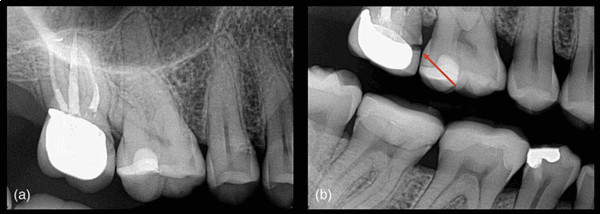

Периапикальные рентгенограммы в настоящее время являются основным инструментом для рентгенографической оценки периапикальных тканей. Это быстрый и простой метод, позволяющий относительно легко интерпретировать данные. Кроме того, он характеризуется и высоким разрешением. Ограничениями периапикальной рентгенографии являются наложение соседних анатомических структур, двухмерный характер изображения и геометрическое искажение (Рисунок 1). Эти факторы приводят к менее чем идеальной чувствительности.

Рисунок 1 Геометрические искажения. (а) Периапикальная рентгенограмма пролеченного первого верхнего правого моляра не выявляет ничего неблагоприятного, (b) однако, при изменении угла рентгенограммы выявляется нарушение краевого прилегания (красная стрелка).